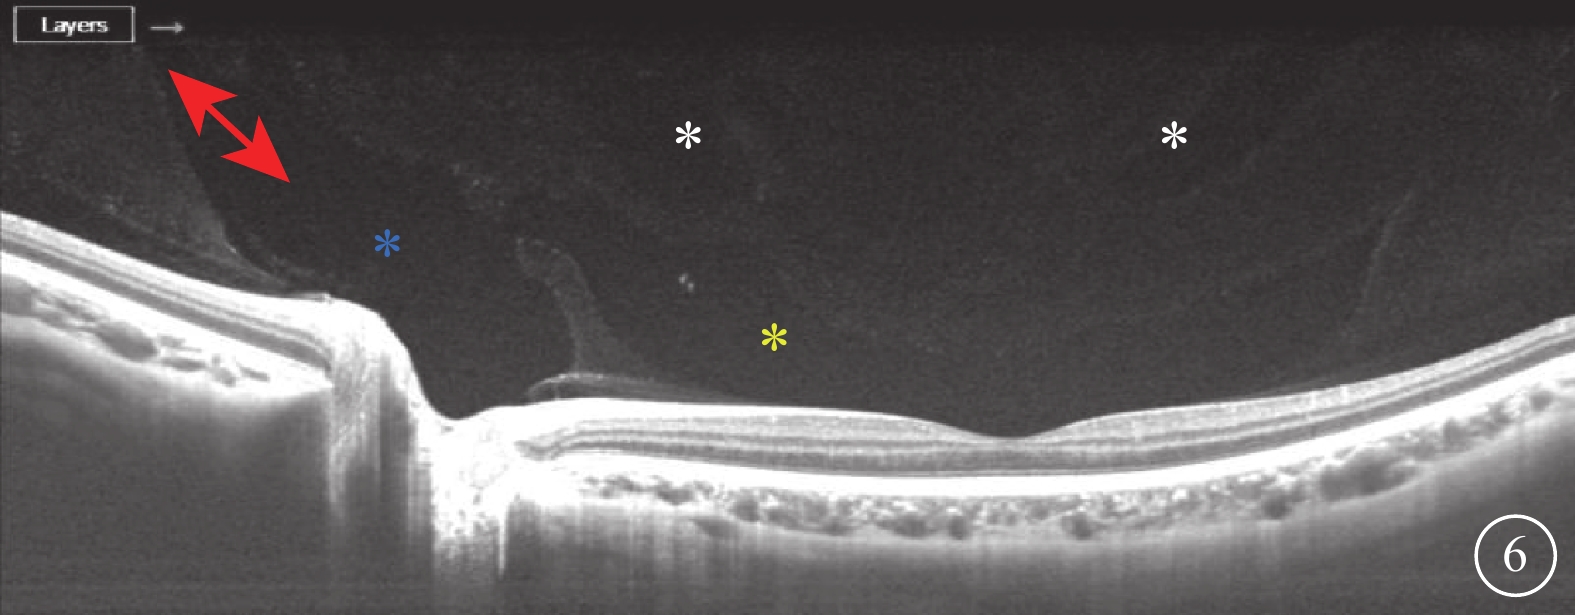

SS-OCT檢查結果顯示,所有受檢眼均在同一掃描層面觀察到PPVP與Martegiani區(圖6),其中PPVP與Martegiani區存在連接通道54只眼(77.0%)。其形態特點與SD-OCT檢查所見相似,但PPVP成像更清晰,與Martegiani區的連接通道更清楚(圖6)。PPVP前存在黃斑上囊7只眼。PPVP伴PVD 4只眼,其中玻璃體后皮質破裂后界不完整(圖7)2只眼。同時行SD-OCT及SS-OCT檢查的24只眼中,SD-OCT、SS-OCT檢查發現PPVP與Martegiani區連接通道分別為18、21只眼;SD-OCT檢查未發現黃斑上囊2只眼,但SS-OCT檢查發現存在。

圖6

受檢眼SS-OCT像。可見PPVP(黃星)與Martegiani區(藍星),以及完整的PPVP和Martegiani區,cloquet管向前延伸(紅色雙箭),玻璃體成像更加平滑、清晰,黃斑上囊結構也更易識別(白色星)

圖6

受檢眼SS-OCT像。可見PPVP(黃星)與Martegiani區(藍星),以及完整的PPVP和Martegiani區,cloquet管向前延伸(紅色雙箭),玻璃體成像更加平滑、清晰,黃斑上囊結構也更易識別(白色星)

SS-OCT檢查結果顯示,所有受檢眼均在同一掃描層面觀察到PPVP與Martegiani區(圖6),其中PPVP與Martegiani區存在連接通道54只眼(77.0%)。其形態特點與SD-OCT檢查所見相似,但PPVP成像更清晰,與Martegiani區的連接通道更清楚(圖6)。PPVP前存在黃斑上囊7只眼。PPVP伴PVD 4只眼,其中玻璃體后皮質破裂后界不完整(圖7)2只眼。同時行SD-OCT及SS-OCT檢查的24只眼中,SD-OCT、SS-OCT檢查發現PPVP與Martegiani區連接通道分別為18、21只眼;SD-OCT檢查未發現黃斑上囊2只眼,但SS-OCT檢查發現存在。

圖6

受檢眼SS-OCT像。可見PPVP(黃星)與Martegiani區(藍星),以及完整的PPVP和Martegiani區,cloquet管向前延伸(紅色雙箭),玻璃體成像更加平滑、清晰,黃斑上囊結構也更易識別(白色星)

圖6

受檢眼SS-OCT像。可見PPVP(黃星)與Martegiani區(藍星),以及完整的PPVP和Martegiani區,cloquet管向前延伸(紅色雙箭),玻璃體成像更加平滑、清晰,黃斑上囊結構也更易識別(白色星)